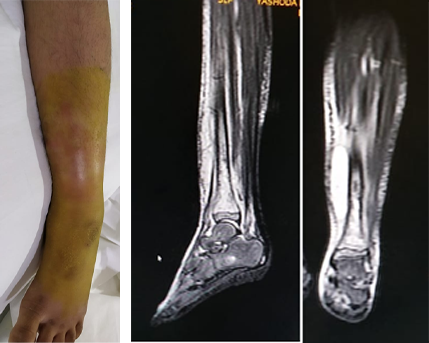

Pre Operative clinical image showing significant swelling and redness & MRI showing intraosseous, subperiosteal and subcutaneous collection.

After

6 month follow up clinical image and X rays showing no leg length descripancy and healed wound.